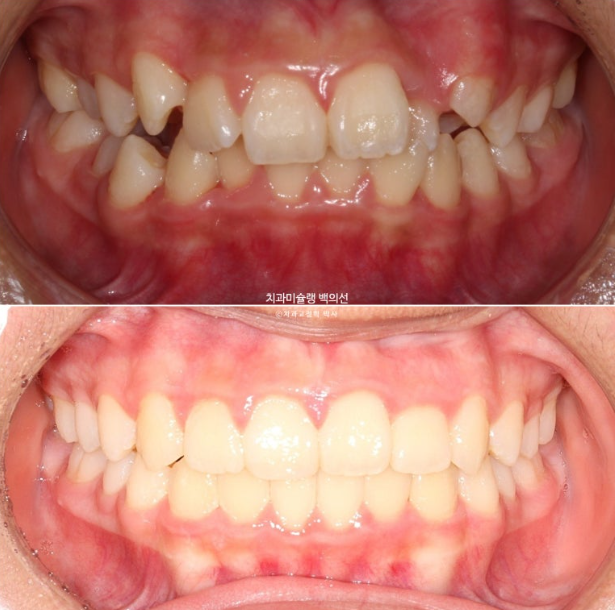

24.02~25.07

24년 1월 교정치료를 위해 온 만 10세 어린이입니다.

중심선이 약 2mm 어긋나 있고 위 앞니 치축은 한쪽으로 기울어져 있습니다.

앞니가 깊게 물리는 과개교합도 보입니다.

중심선은 개선되었으나 약간의 불일치가 남아있으며 반대교합과 덧니는 모두 개선되었습니다.

중심선은 잘 맞고

어금니 교합은 물샐틈 없는 1급 교합관계를 보입니다.

이제 전 후 비교해 보겠습니다.

총 치료기간은 1년 6개월이고 중간에 중심선 이슈로 잠시 쉬는 시간이 4개월 있었습니다.

재제작은 총 2회 했습니다.

치료결과가 어린이 교정이 아닌 정식 성인교정 치료 결과에 준한만큼 유지장치도 철저히 들어갑니다.

어긋난 중심선이 맞아졌으며 기울어진 앞니 치축도 좋아졌습니다.

앞니가 깊게 물리는 과개교합도 좋아졌습니다.